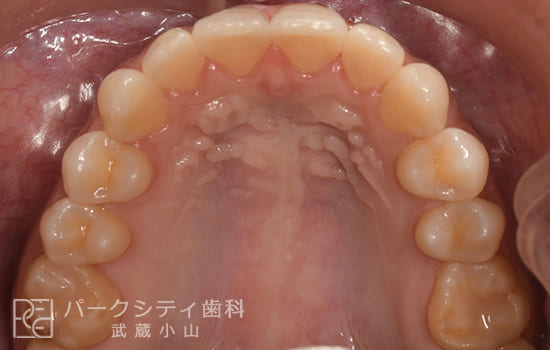

前歯の歯並びを部分矯正で治した症例

- 主訴

- 前歯の歯並びが気になる

- 治療法

- 舌側矯正による部分矯正

- 治療期間

- 6か月

- 費用

- ¥532,400

【内訳】

検査料:¥33,000

装置料:¥220,000×2(上下)

チェック:¥4,400×6

保定装置:¥16,500×2(上下)

上下裏側に装置をつけ、歯と歯の間を少しずつ削合(ディスキング)しながら歯並びを整えて、約6か月で保定へ移行しました。